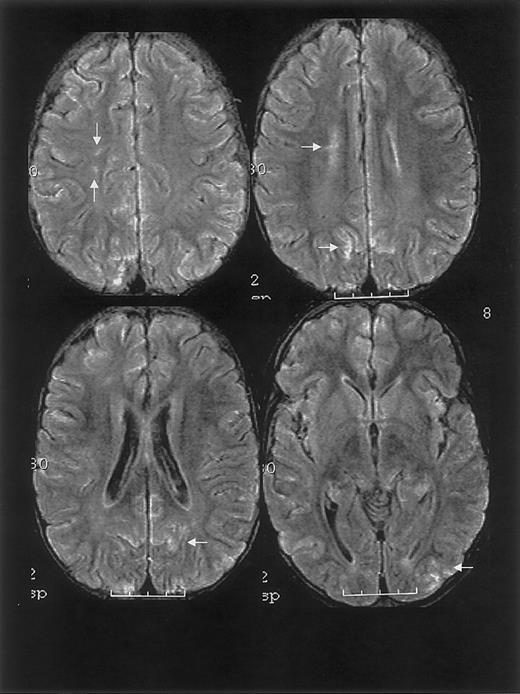

One year prior to ACS episode, the patient had a normal MRI study. MRI on hospital day 20 and 2.5 months following discharge revealed findings consistent with RPLS and silent cerebral ischemia (Figure 1).

MRI findings for case 1.

Multifocal areas of fluid-attenuated inversion recovery (FLAIR) T2-weighted signal abnormality in the subcortical white matter and overlying gray matter of the frontal, parietal, and occipital lobes (bottom).

One year prior to ACS episode, the patient had normal MRI/MRA and transcranial Doppler studies. MRI on day 10 and 1 month following discharge revealed RPLS with superimposed ischemic white matter changes (Figure 2).

MRI findings for case 2.

Multifocal areas of signal hyperintensity predominantly limited to the cortex of the posterior parietal and occipital lobes on FLAIR T2-weighted images, including punctate areas of abnormality in the deep, periventricular white matter of the right frontal lobe and of the cortex of the right medial parietal lobe. MRI done 1 month following discharge revealed punctate lesions in the frontal lobe, representing subacute to chronic ischemic changes, but resolution of the T2 hyperintense lesions in the posterior distribution.